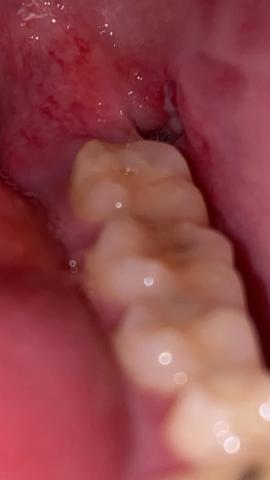

I can see the extraction site (a visible “hole”) behind the last visible tooth with surrounding red tissue.

I don’t clearly see exposed white bone in the socket in this image — which is a common visual sign of a dry socket — but the photo is close and a bit out of focus, so that isn’t definitive.

Some redness and a fairly open socket 4 days after extraction can still be within normal healing, especially if pain is improving or mild.